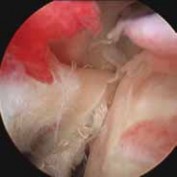

FIG 5 • Arthroscopic débridement of a partial-thickness tear.

2. Arthroscopic débridement is an initial component of nearly every biceps tendon surgical procedure.

1. In cases of fraying or partial tearing, débridement alone may be adequate to eliminate its contribution as a pain generator (

FIG 5

).

2. This is particularly true in cases in which the preoperative workup did not suggest the biceps as a significant component of patient symptoms, and when concomitant pathology may otherwise explain the patient’s presentation.